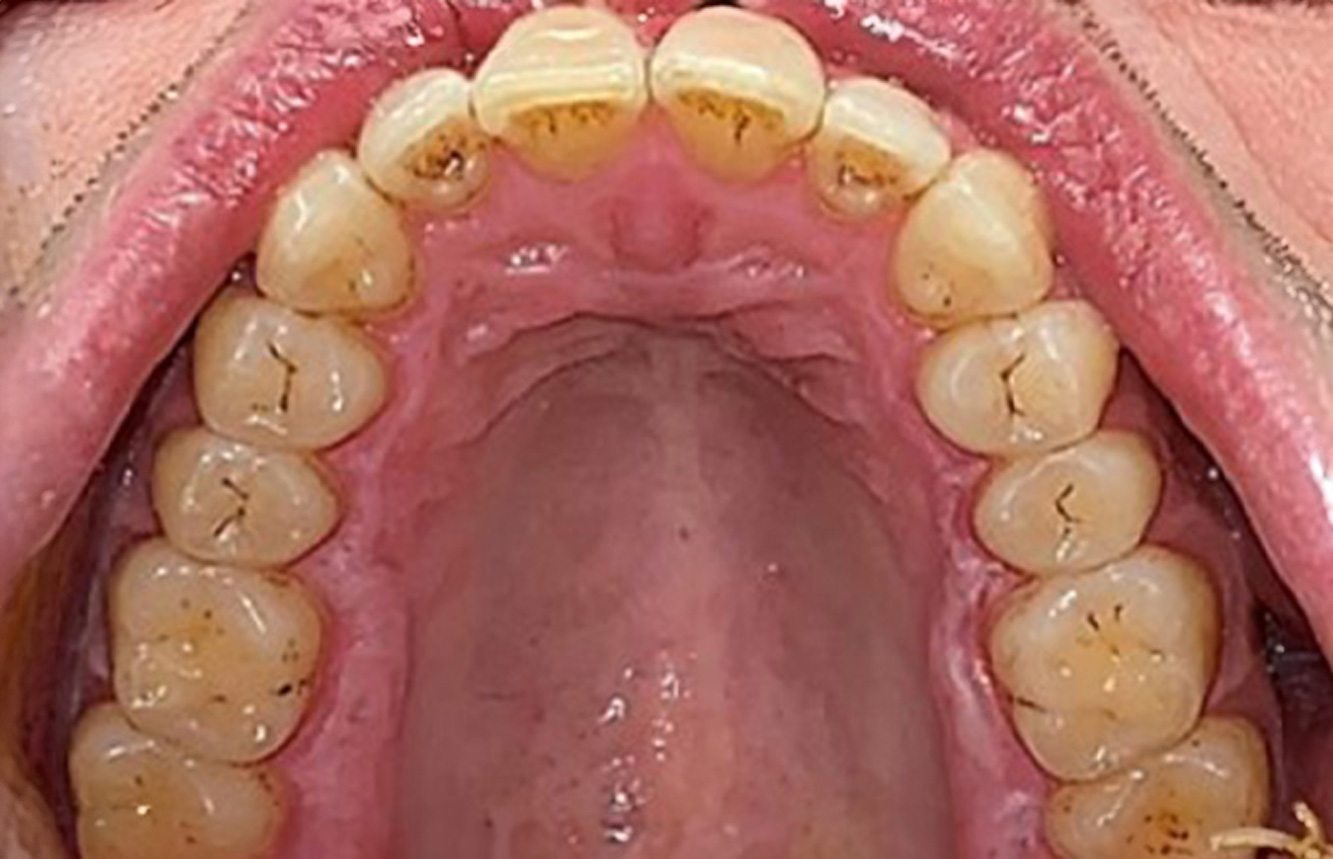

The (orally) healthy patient with implants

In the medical history, the 55-year-old patient states that he has no systemic disease and is not taking any medication. The patient’s lifestyle is similarly unremarkable. The patient has a few tooth restorations and two implants (2nd and 4th quadrants). On the basis of current findings, gingivitis is identified in an otherwise stable periodontal condition on the reduced periodontium (stage III, grade A). more

Pacient sănătos cu boală parodontală incipientă

Pacientul în vârstă de 68 de ani nu are nicio afecțiune generală și nu ia niciun medicament care ar putea fi relevant pentru sănătatea sa orală, iar stilul său de viață nu prezintă niciun risc special. Pacientul are două implanturi dentare (cadranul 3, de cinci ani) și un caz anterior de boală parodontală (stadiul IV, gradul B) cu pierderea dinților. În prezent, condițiile parodontale sunt stabile. Cu toate acestea, parodontoza crește semnificativ complicațiile biologice ale implanturilor și există riscul de pierdere a implanturilor (21). Se pot determina patru recomandări pentru ședința de profilaxie. mai multe